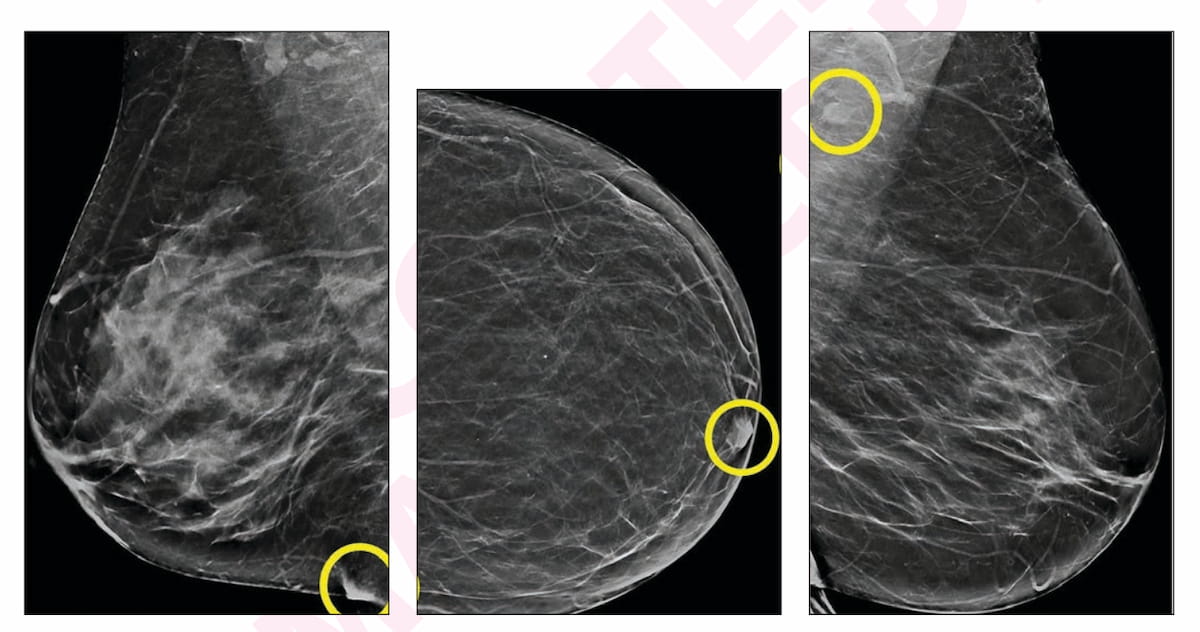

Here one can see an inflammatory skin fold (A), a nipple not in profile (B) and a benign-appearing axillary lymph node (C) in synthetic views from false-positive digital breast tomosynthesis (DBT) exams in different patients. For these AI-only flagged findings, none of these patients had a breast cancer diagnosis within one year of the exams. (Images courtesy of the American Journal of Roentgenology.)